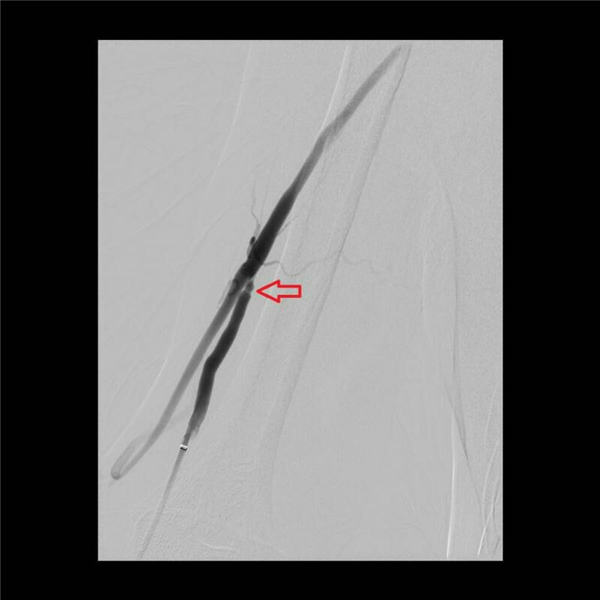

随后,两位主任通力协作,通过放置球囊扩张的方法,对血管的三处狭窄段分别用球囊扩张后,可见狭窄段部分或者完全扩张(下图红色箭头所示)。